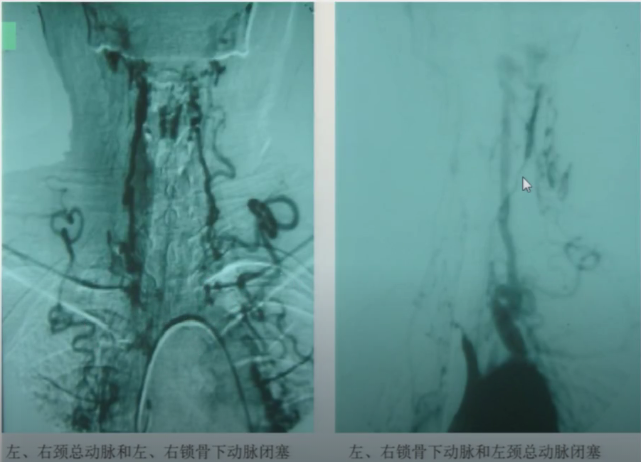

➤ 动脉炎

受累器官组织缺血症状,全身症状,炎性指标;影像学上广泛受累,向心性狭窄,管壁均匀强化,代偿增生。

图14